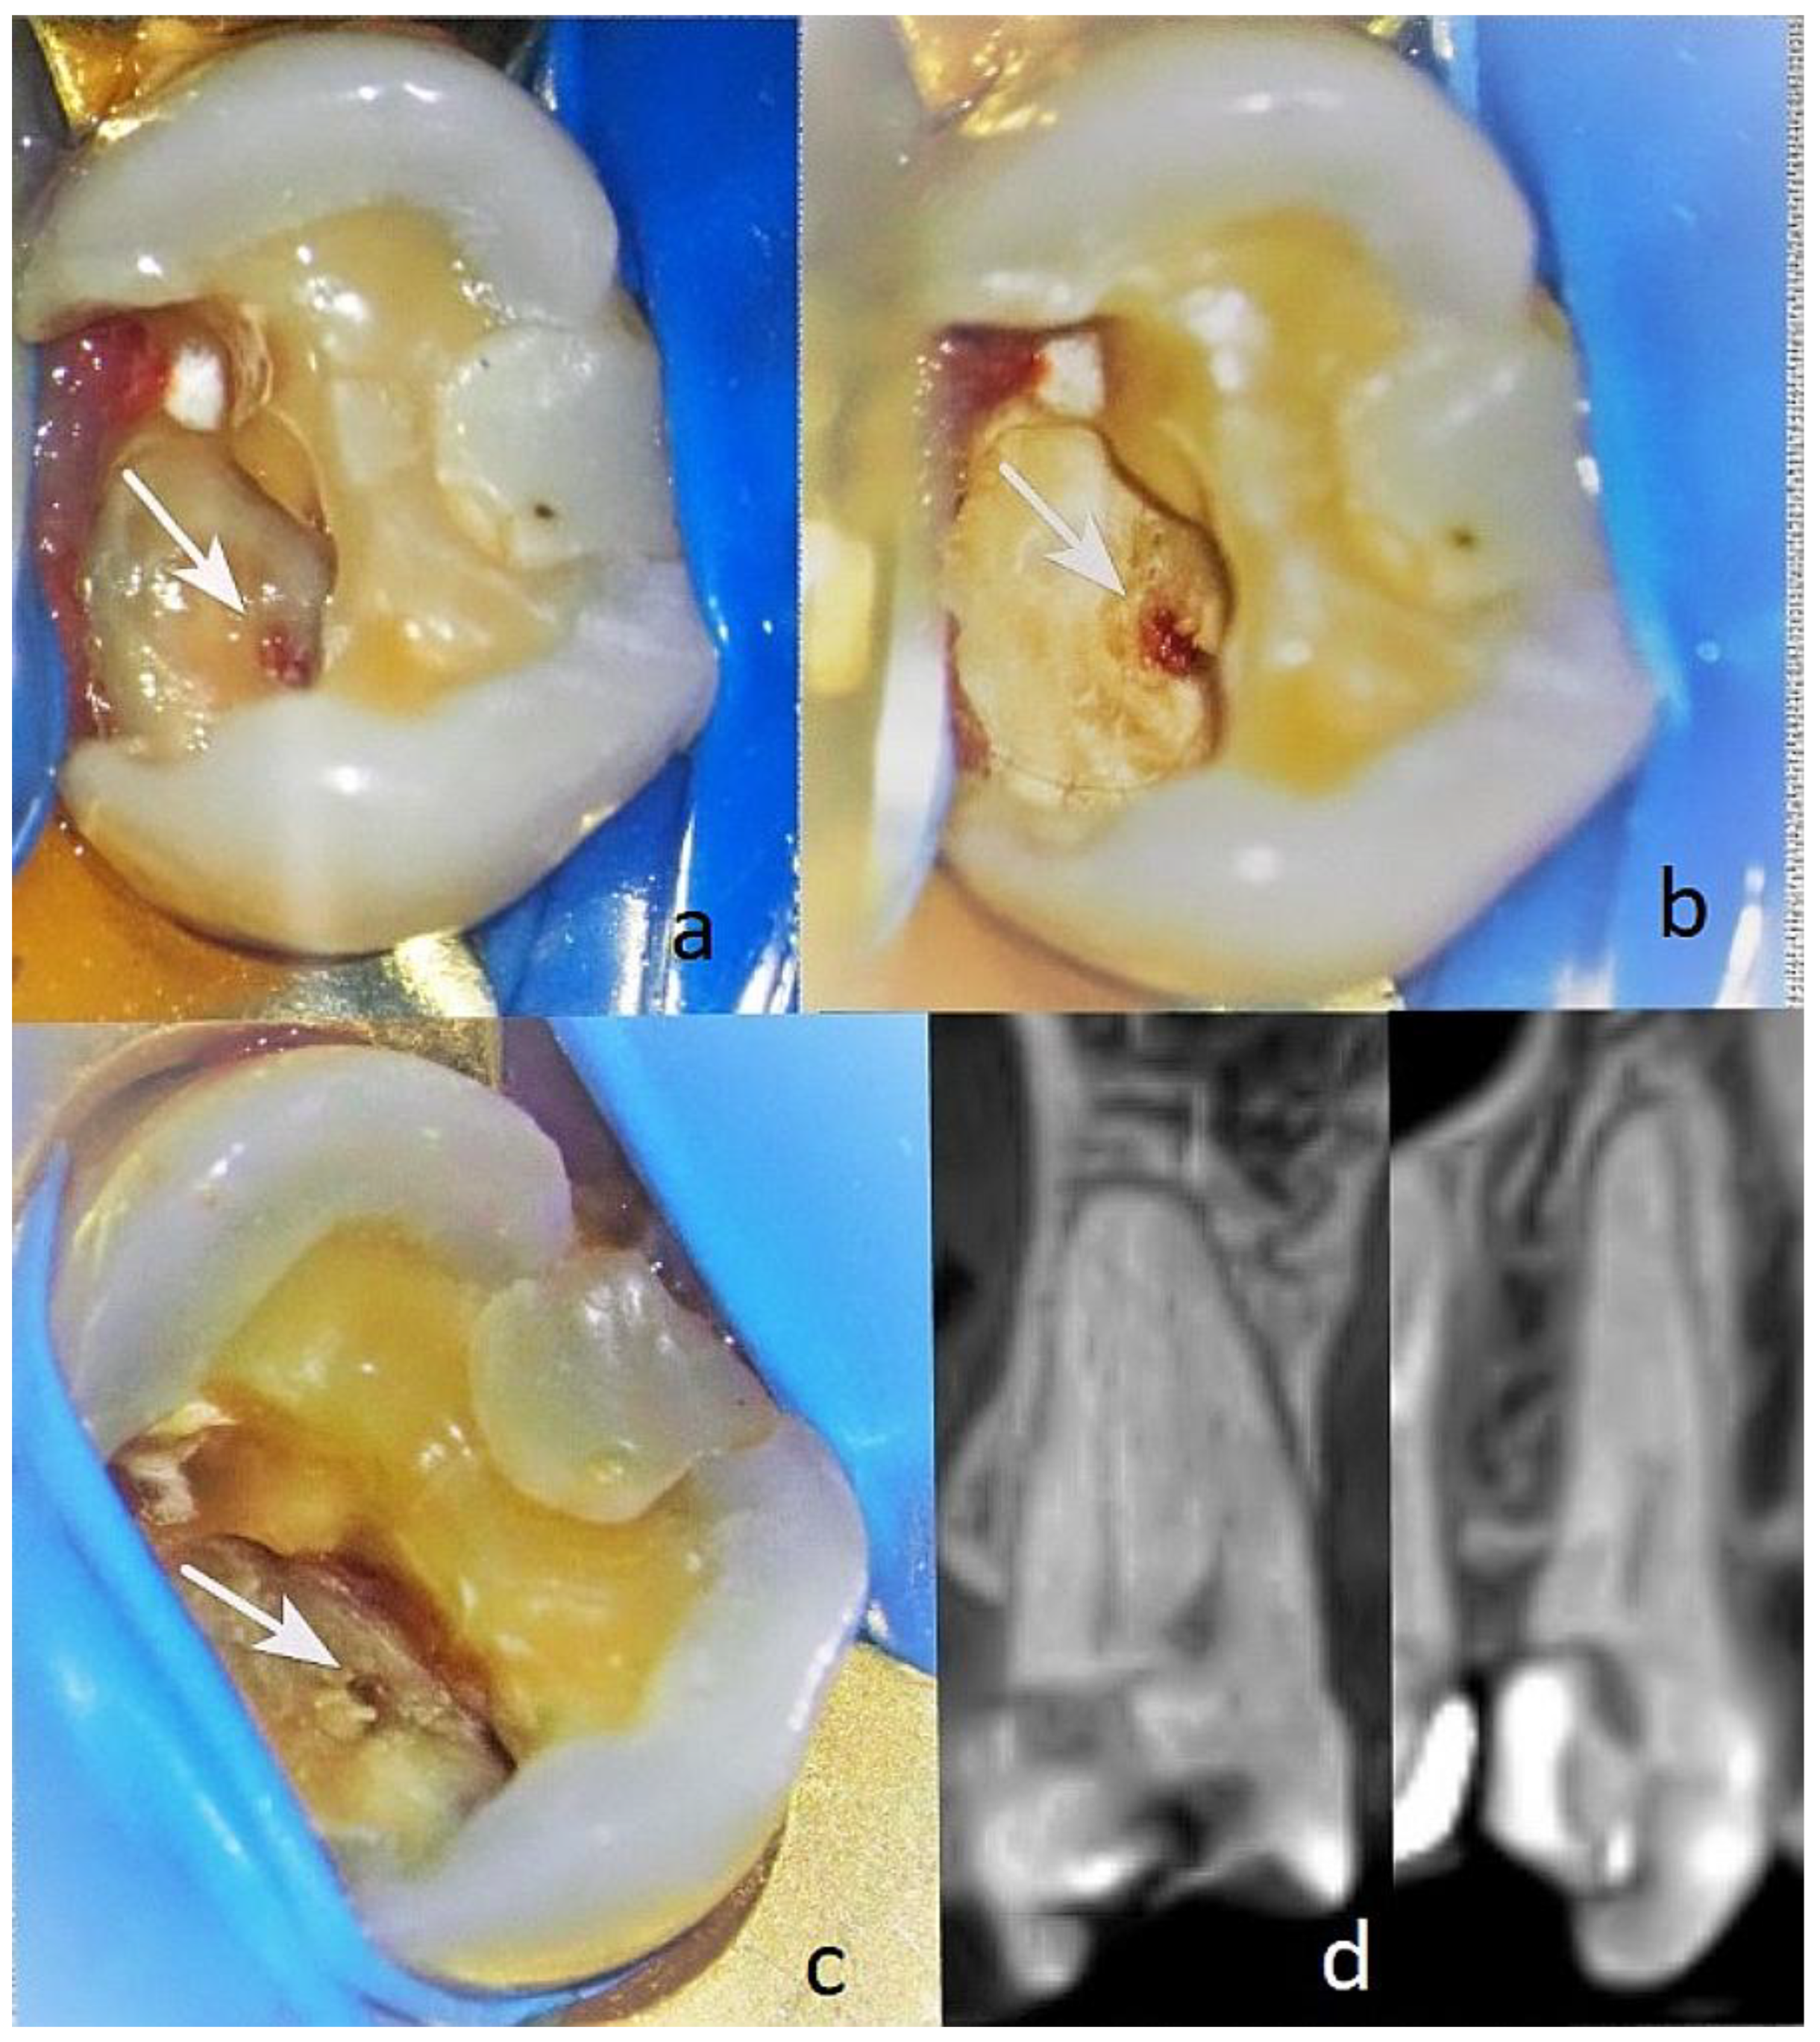

3.1.3. Clinical Case N16

Patient AB, 65 years old. Diagnosis: reversible pulpitis of tooth 14. The patient reported symptoms of hot and cold sensitivity for one month. She identified the causative tooth and reported that, after removing the irritant, the pain subsided within 2–3 s. She also reported a spontaneous pain episode in the evening. Upon examination, a large filling was found distally and a small one mesially. During probing distally, a gap between the filling and the tooth tissue was established distally in the area of the gums with EPT -19µA at the cervical area buccally. The pulse oximetry was 87%. Through microscopic examination, the pulp communication was found to measure about <1.5 mm, and the tissue colour was pink and at the level of the surrounding dentin (Figure 8a). Pulp wound haemostasis and cavity disinfection with ozone gas was performed for 18 s using an ozone generator (i.e.Figure 8(b).

Control EPT testing was conducted at one, three, and six months with EPT values of 18 µA, 14 µA, and 10 µA, and the pulse oximetry measurement was 83%. In the sixth month, the Biodentine was removed, and reparative dentin deposition was found in the area of communication (Figure 8(c)). The formed dentinal bridge was visible in the CBCT examination (Figure 8(d)). The GIC was also removed, and a final restoration was placed.

3.1.4. Clinical Case N4

A 27-year-old female patient (RL) presented for treatment of tooth 37 with a diagnosis of reversible pulpitis (EPT 17 μA). The caries were located on the entire buccal surface, including the cervical area, as well as on the occlusal and medial surfaces of the dental crown. Upon cleaning the infected dentin from the buccal side, a communication with the dental pulp was found, approximately <1 mm in size with very slight bleeding (Figure 9(a)). No pulse oximetry examination was performed, as preserving the buccal wall is required.

The communication was located close to the buccal vestibular pulp horn. The pulp lesion was pale pink to reddish and was on the same level as the surrounding dentin. The dentin above the pulp lesion was healthy; however, below it, there were remnants of leathery dentin.

Under anaesthesia, haemostasis of the pulp wound and disinfection of the cavity with ozone gas was performed for 18 s. The protocol for preparing the biocompatible material AB was as described above, as well as for the pulp communication. The cavity was sealed with glass ionomer cement (Fuji LC II, Japan Int. Corp.). The patient complained of spontaneous pain for the next two days, with intervals of a few minutes, without the need for medication. After 3 months, the treated tooth was asymptomatic. The paraclinical findings of the EPT were 6 μA (Figure 9(b)). A final filling was placed. The tooth was monitored up to 12 months and showed clinically preserved vitality.

Figure 8. (a) View of the cleaned carious cavity free of infected dentin with an arrow indicating the location of the communication; (b) view of the dentin wound after ozonation for 18 s with an arrow indicating the location of the communication; (c) view of the dentin wound after five months with an arrow indicating the location of the communication covered with reparative dentin; (d) CBCT of tooth 14 after five months in two projections before removal of the temporary restoration at six months, which shows the deposition of reparative dentin.

Figure 9. (a) The revealed cavity: the communication with the dental pulp is marked with a white arrow; (b) three months after the placement of the biomaterial from AB (A-PRF+): the communication with the dental pulp covered with a thin layer of reparative dentin is marked with a white arrow.